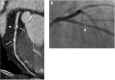

Purpose: Coronary bioresorbable stents (BRS) do not produce blooming artifacts on computed tomography (CT), in contrast to metallic stents, as they are made of a bioresorbable polymer and are radiolucent. They allow to evaluate the coronary plaque beneath. The low-attenuation plaque (LAP) suggests plaque vulnerability and is CT assessable. The aim of our study was to show the possibility of a non-invasive CT evaluation of the volume and the LAP composition of the intra- and juxta-stent plaque.

Methodology: In our prospective longitudinal study, we recruited 27 consecutive patients (35 BRS stents total; mean age 60 +/- 9 years) with bioresorbable stents for a 256-slice ECG-synchronized CT evaluation at 1- and 12-months post stent implantation. Total plaque volume (mm3), absolute and relative (%) LAP volume per block in the pre- intra- and post-stent zones were analyzed; comparison 1- and 12-months post-implantation of BRS. Changes in the previously mentioned variables were assessed by the mixed effects models with and without spline, which also accounted for the correlation between repeated measurements.